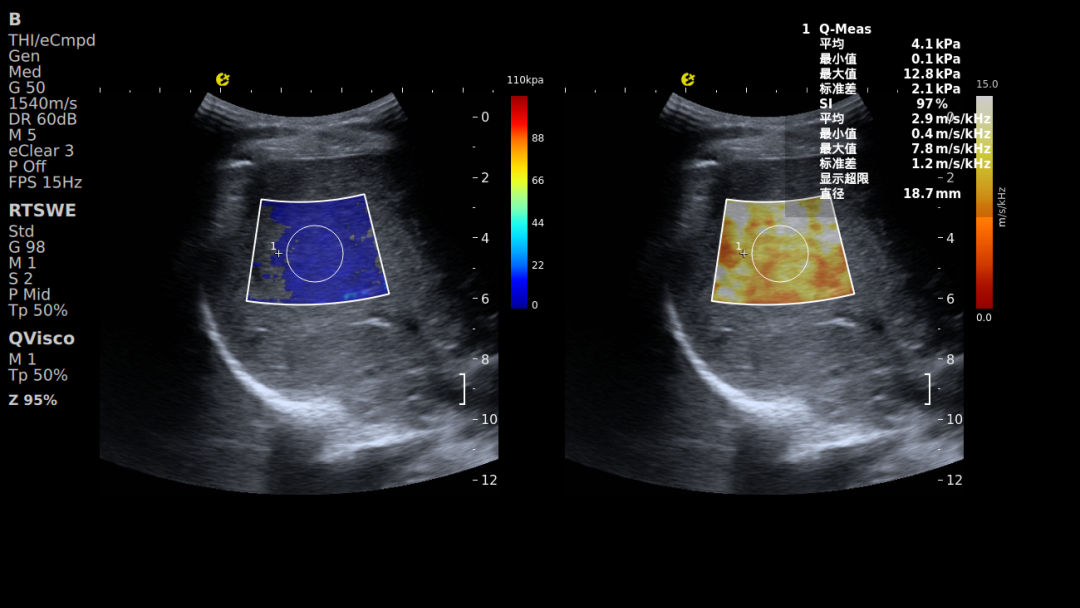

人体肝脏部位的E成像(RTSWE,左)

剪切波频散成像(SWD,中) 黏弹性成像(Viscoelastic,右)

黏弹性定量成像-QVisco™

可精准揭示肝脏组织微观病理改变,清晰呈现肝脏从“可逆功能异常”到“不可逆结构改变”的整个病理过程。该参数能够评估细胞水肿、炎症浸润及脂质堆积等细微变化,有效弥补了传统弹性技术对微观病变与炎症活动识别能力的不足,为肝脏病理分层提供了新的影像维度,已被多项临床研究证实其应用价值。